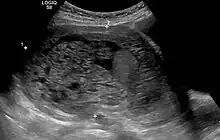

The diagnosis is strongly suggested by ultrasound (sonogram), but definitive diagnosis requires histopathological examination. On ultrasound, the mole resembles a bunch of grapes ("cluster of grapes" or "honeycombed uterus" or "snow-storm").[14] There is increased trophoblast proliferation and enlarging of the chorionic villi, and angiogenesis in the trophoblasts is impaired.[15]

Molar pregnancy in ultrasound